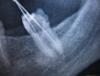

Mila* Опубликовано 5 марта, 2010 Автор Поделиться Опубликовано 5 марта, 2010 Оказалось - киста на 7-м нижнем зубе. Он впервые пролечен в конце декабря. Вопрос: может ли данное воспаление и образование кисты быть следствием занесения инфекции 2 месяца назад, или это слишком небольшой срок для развития кисты, и она была там раньше, невидимая на снимках, как сказала мне доктор? И еще вопрос, по сабжу.При перелечивании канала доктор попала в эту кисту.По ее реакции я не уверена, что это было сделано умышленно.На вопрос: хорошо это для лечения или нет, она не ответила, т.е. уклонилась от ответа. Сказав, что пошлет меня к хирургу, т.к. лучше сделать операцию.Канал, который ближе к центру, пройден ей повторно, а второй канал - нет.Лечение назначено: трихопол, клартин, полоскание р-ром йодированной соли. Прокомментируйте, пожалуйста, ситуацию.Снимок с иглой есть, попробую его переснять. Ссылка на комментарий

Mila* Опубликовано 7 марта, 2010 Автор Поделиться Опубликовано 7 марта, 2010 стрелками я пометила изменения на медиальном корне, но если присмотреться и на дистальном они тоже есть.Снежана,спасибо.Добавлю, что между депульпированием и этим снимком - прошел один месяц.А на том снимке, который делался в день лечения - никаких затемнений еще нет. Посмотрите, пожалуйста, его. И, естественно, меня никто ни о чем не предупреждал. Комментировать шансы я не буду, слишком от многого это зависит.Хотя бы конспективно, списком.Что видно на втором снимке? Ссылка на комментарий

Снежана Опубликовано 7 марта, 2010 Поделиться Опубликовано 7 марта, 2010 конспективно: от навыков врача, оснащения кабинета, возможностей вашего организма.на этом снимке ничего не видно, но по опыту, такие деструкции как у вас за пару месяцев не образуются, все таки нужен больший срок. Есть немалое количество случаев у разных докторов, когда рентген давал картину мнимого благополучия. Ссылка на комментарий

Fred Опубликовано 8 марта, 2010 Поделиться Опубликовано 8 марта, 2010 Снежана,спасибо.Добавлю, что между депульпированием и этим снимком - прошел один месяц.А на том снимке, который делался в день лечения - никаких затемнений еще нет. Посмотрите, пожалуйста, его. И, естественно, меня никто ни о чем не предупреждал. Хотя бы конспективно, списком.Что видно на втором снимке? Коффердама нет, зубу "кирдых", как еще никто не заметил этого? Ссылка на комментарий

Mila* Опубликовано 8 марта, 2010 Автор Поделиться Опубликовано 8 марта, 2010 зубу "кирдых", Fred, как "кирдых", почему? Ссылка на комментарий

Fred Опубликовано 8 марта, 2010 Поделиться Опубликовано 8 марта, 2010 Fred, как "кирдых", почему?В зуб же иголочки сували без специальной резинки, на рот натянутой. А это все, критично, все зубы, которые лечат без волшебной резинки, в скором будущем удаляются. Верите в это? Ссылка на комментарий